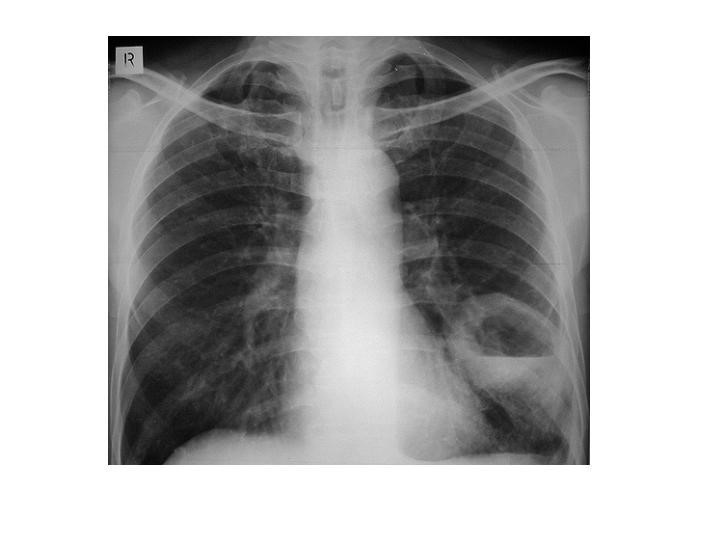

60yo female with history of congestive heart failure presents to the clinic with a 3 week history of worsening SOB

View

DX: pleura effusion